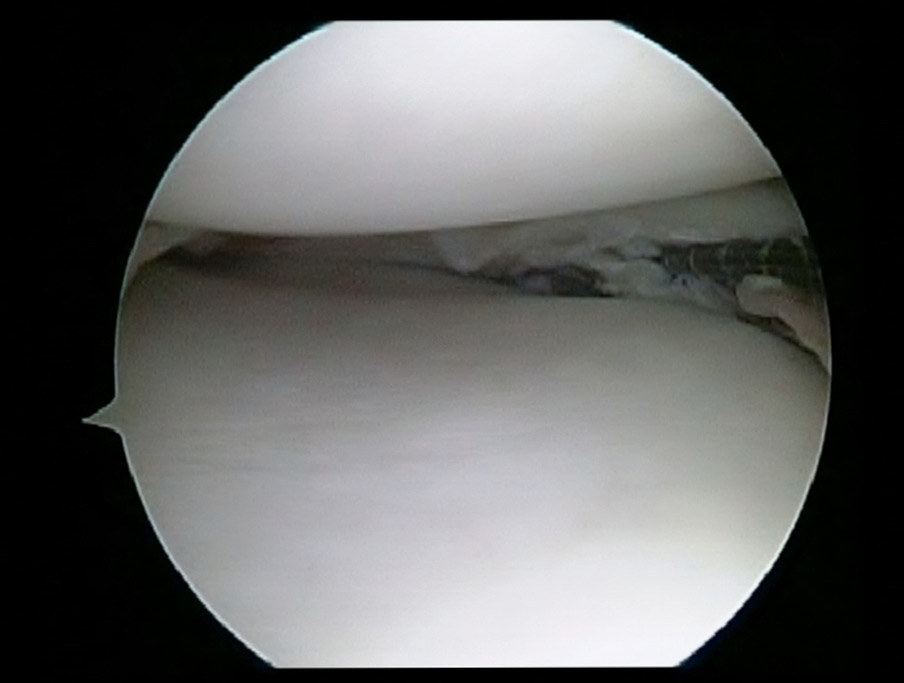

ACL reconstruction Knee Arthroscopy Dr Sujit Jos DOCJOINTS//DR

ACL reconstruction Knee Arthroscopy Dr Sujit Jos DOCJOINTS//DR How Long To Ice Knee After Arthroscopic Surgery Continue to ice the knee to reduce pain and swelling. • do this every day for the first 3 days after your surgery. avoid walking for long distances for 4 to 6 weeks after surgery. the recovery process and timeline after arthroscopic knee surgery depend on several factors, such as the. Ice helps with the swelling and can. How Long To Ice Knee After Arthroscopic Surgery.